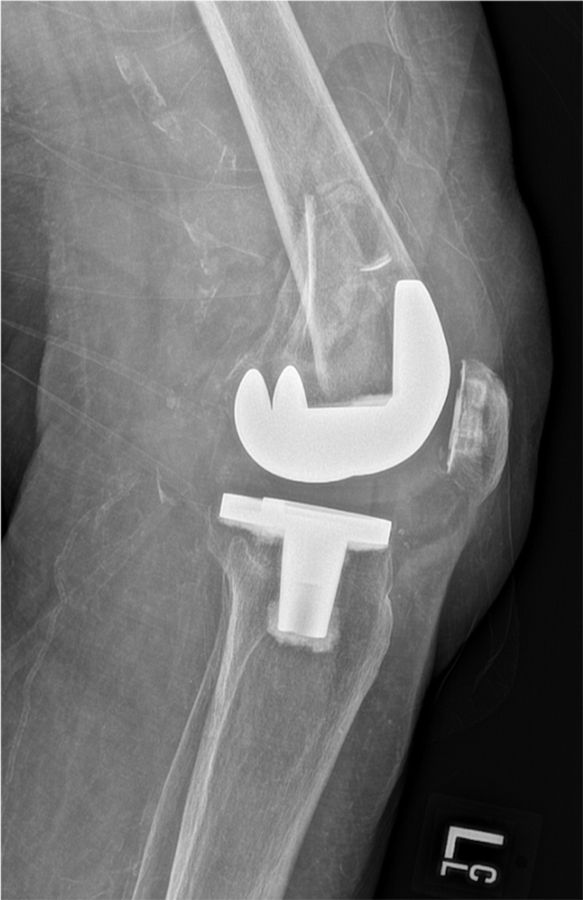

The risk of vascular injury and the difficulty of exposure is less when the femur is subluxated anterior, however, this situation is not without difficulties itself. Usually anterior subluxation of the femur on the tibia results in a significant flexion contracture and significant distal femur resection is needed to allow full extension of the knee and balance flexion and extension space. Based on my personal experience I strongly favor a hinge implant for posttraumatic anterior or posterior dislocations of the femur (Figure 5a, b, c, d).

My rational for this implant choice is that in severe anterior dislocation of the femur, often, the insertion of the collateral ligaments gets compromised when additional distal femur resection is needed to allow full extension. In addition, it is difficult to achieve reliable postoperative range of motion when encountering a knee subluxation in the presence of preoperative stiffness (less than 80 degrees arc of motion). Since the combination of a traumatic dislocation is seldom associated with an addition extraarticular deformity stemmed hinge implants can usually be used without problems.

4. I favor hinge implants for patients with anterior and posterior knee dislocations and an overall arc of motion of less than 80 degrees.